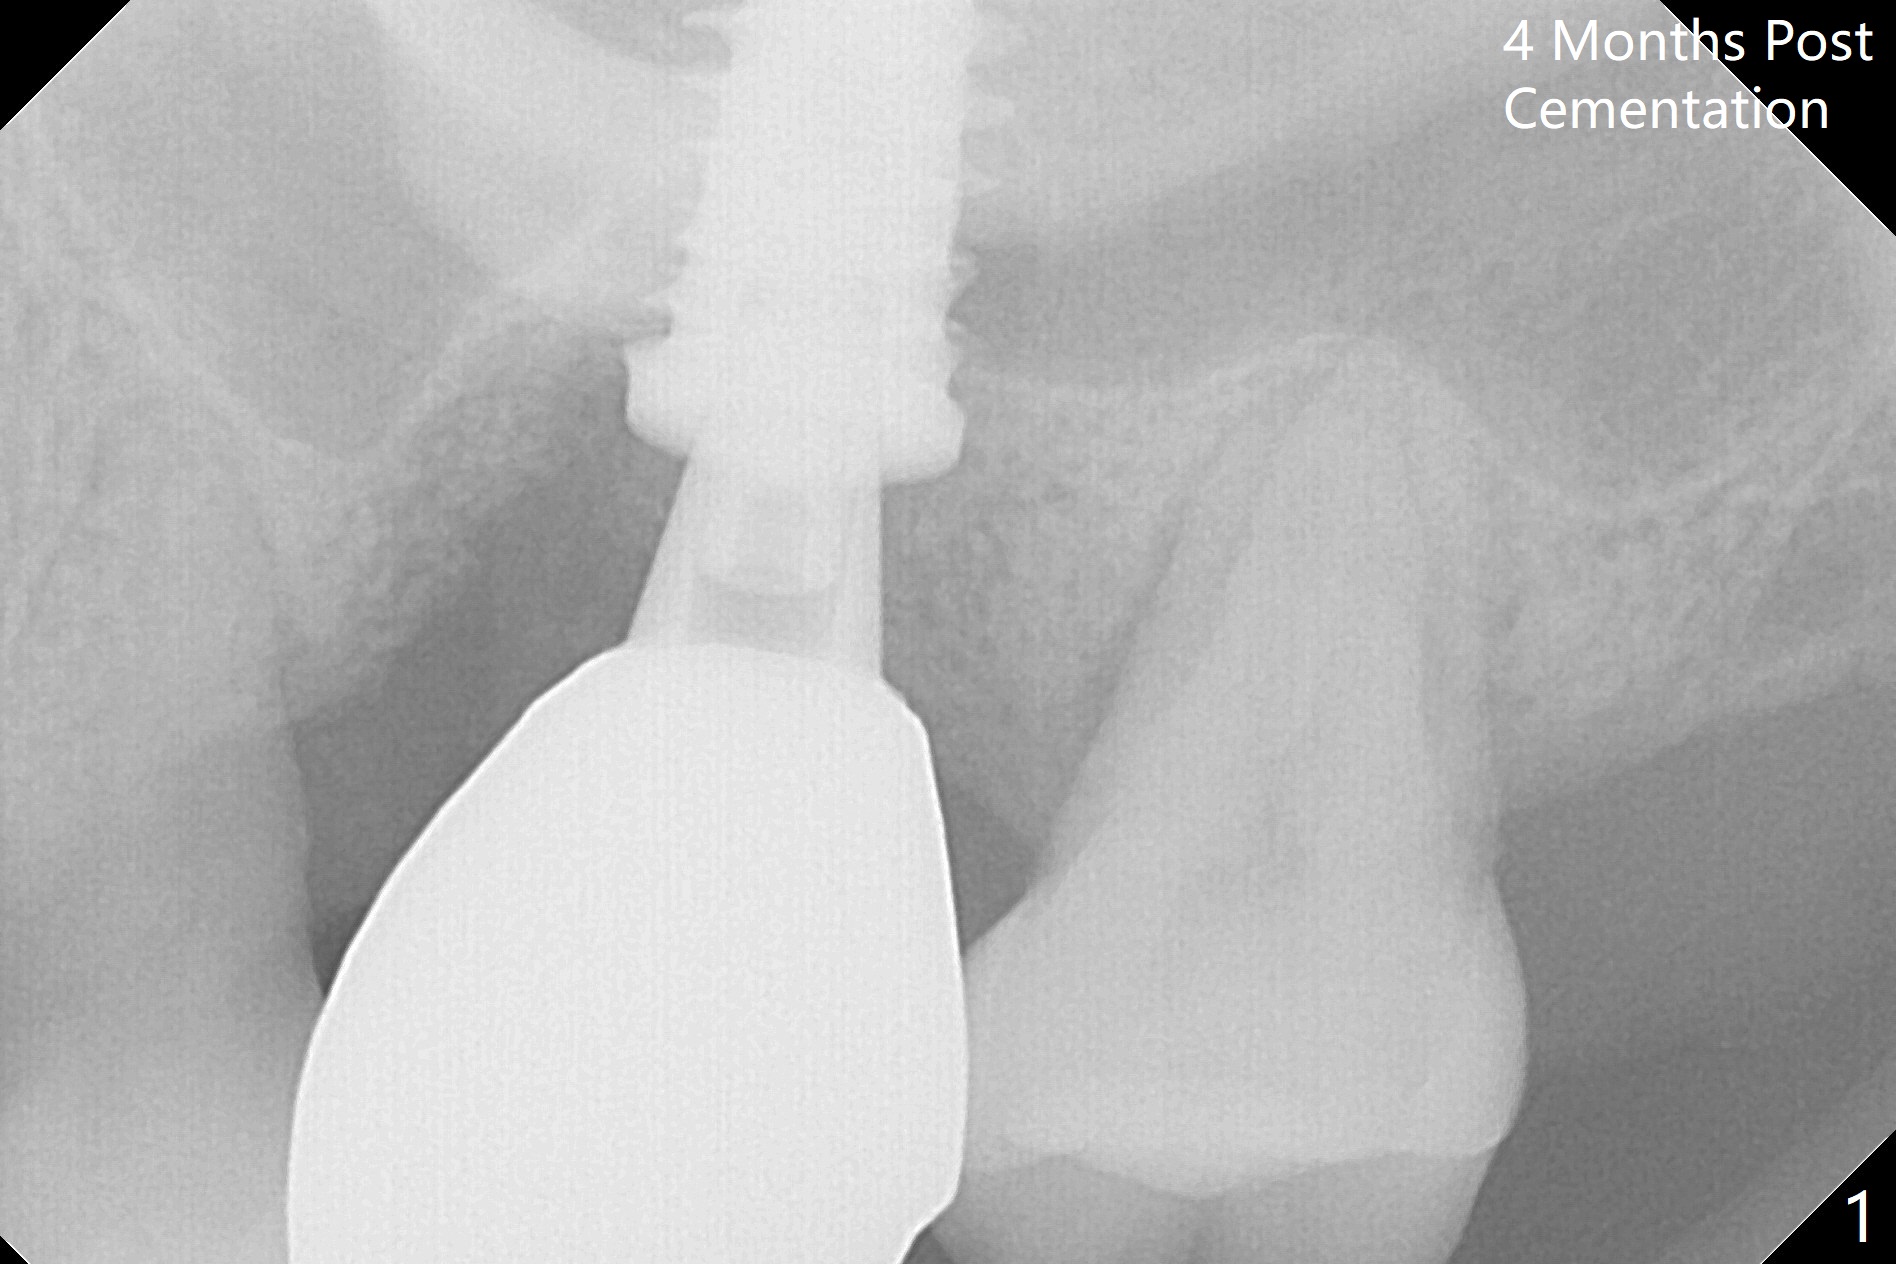

Three months post cementation, the implant at #14 is found loose (Fig.1: 6.5x11 mm) and removed. After removal of minimal granulation tissue, normal saline disappears into the apical end of osteotomy. In fact there is no bone apically, although the sinus membrane is intact. After try in of various taps (tapered and cylindrical, bone- and tissue-level), a 8x14 mm dummy implant is placed (Fig.2), followed by Osteogen plug and the same sized definitive implant, which has to be placed deeper to obtain ~ 45 Ncm (Fig.3). There is minimal thread engagement. If the implant fails, place 2 layers of PRF membrane apically, bone graft and 1 layer of PRF coronally for ridge preservation. A healing abutment will be placed to expose the coronal end of the implant ~ 4 months postop. The tissue-level implant remains subgingival 4.5 months postop (Fig.4). A 8 mm healing cuff cannot be placed even after laser gingivectomy. The implant is 2 mm subcrestal mesially. Torque wrench cannot reverse the implant at 60 Ncm. The implant is later reversed with Tatum wrench until it is turned with the torque wrench at 30 Ncm. The implant remains stable, while the healing cuff with Triple Antibiotic Ointment is placed. The healing cuff is stable 2 weeks later (Fig.5 C). With progressive loading for a month, a crown is cemented 9 months postop. There appears no bone loss 2.5 months post cementation (11 months postop, Fig.6). Return to Upper Molar Immediate Implant, Armaments, IBS #3 Xin Wei, DDS, PhD, MS 1st edition 04/30/2018, last revision 04/14/2019